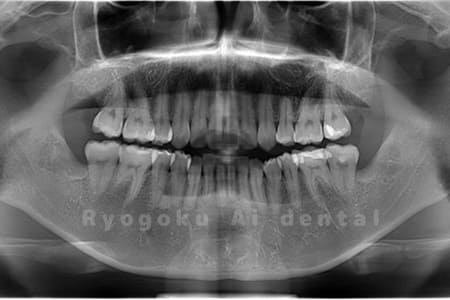

Case02

- 原因

- 下顎の水平埋伏智歯

- 治療内容

- 下顎の水平埋伏智歯を抜歯

<リスク・副作用>

手術後は痛み、腫れ、痺れなどの副作用が生じる場合があります。